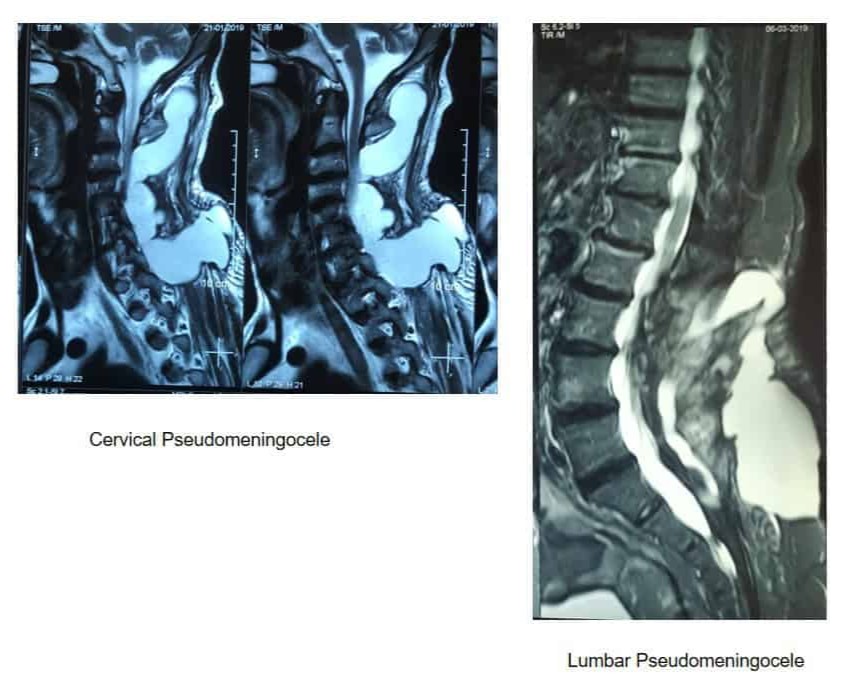

Dural tears in lumbar surgery: persistent and evolving challenge

- Fibrin glue or sealants: In cases where suturing is technically impossible, standalone use of fibrin glue or synthetic polymer-based sealants may be used, although these are associated with slightly higher pseudomeningocele rates.

CSF leak monitoring: Early signs of complications include headache, nausea, clear wound drainage, or radicular symptoms. MRI or CT myelography may be necessary to diagnose pseudomeningocele or fistula.

Reoperation indications: Persistent leaks, expanding pseudomeningoceles, or signs of meningitis warrant prompt reintervention. In select cases, percutaneous fibrin patch injection under imaging guidance may offer nonoperative resolution.